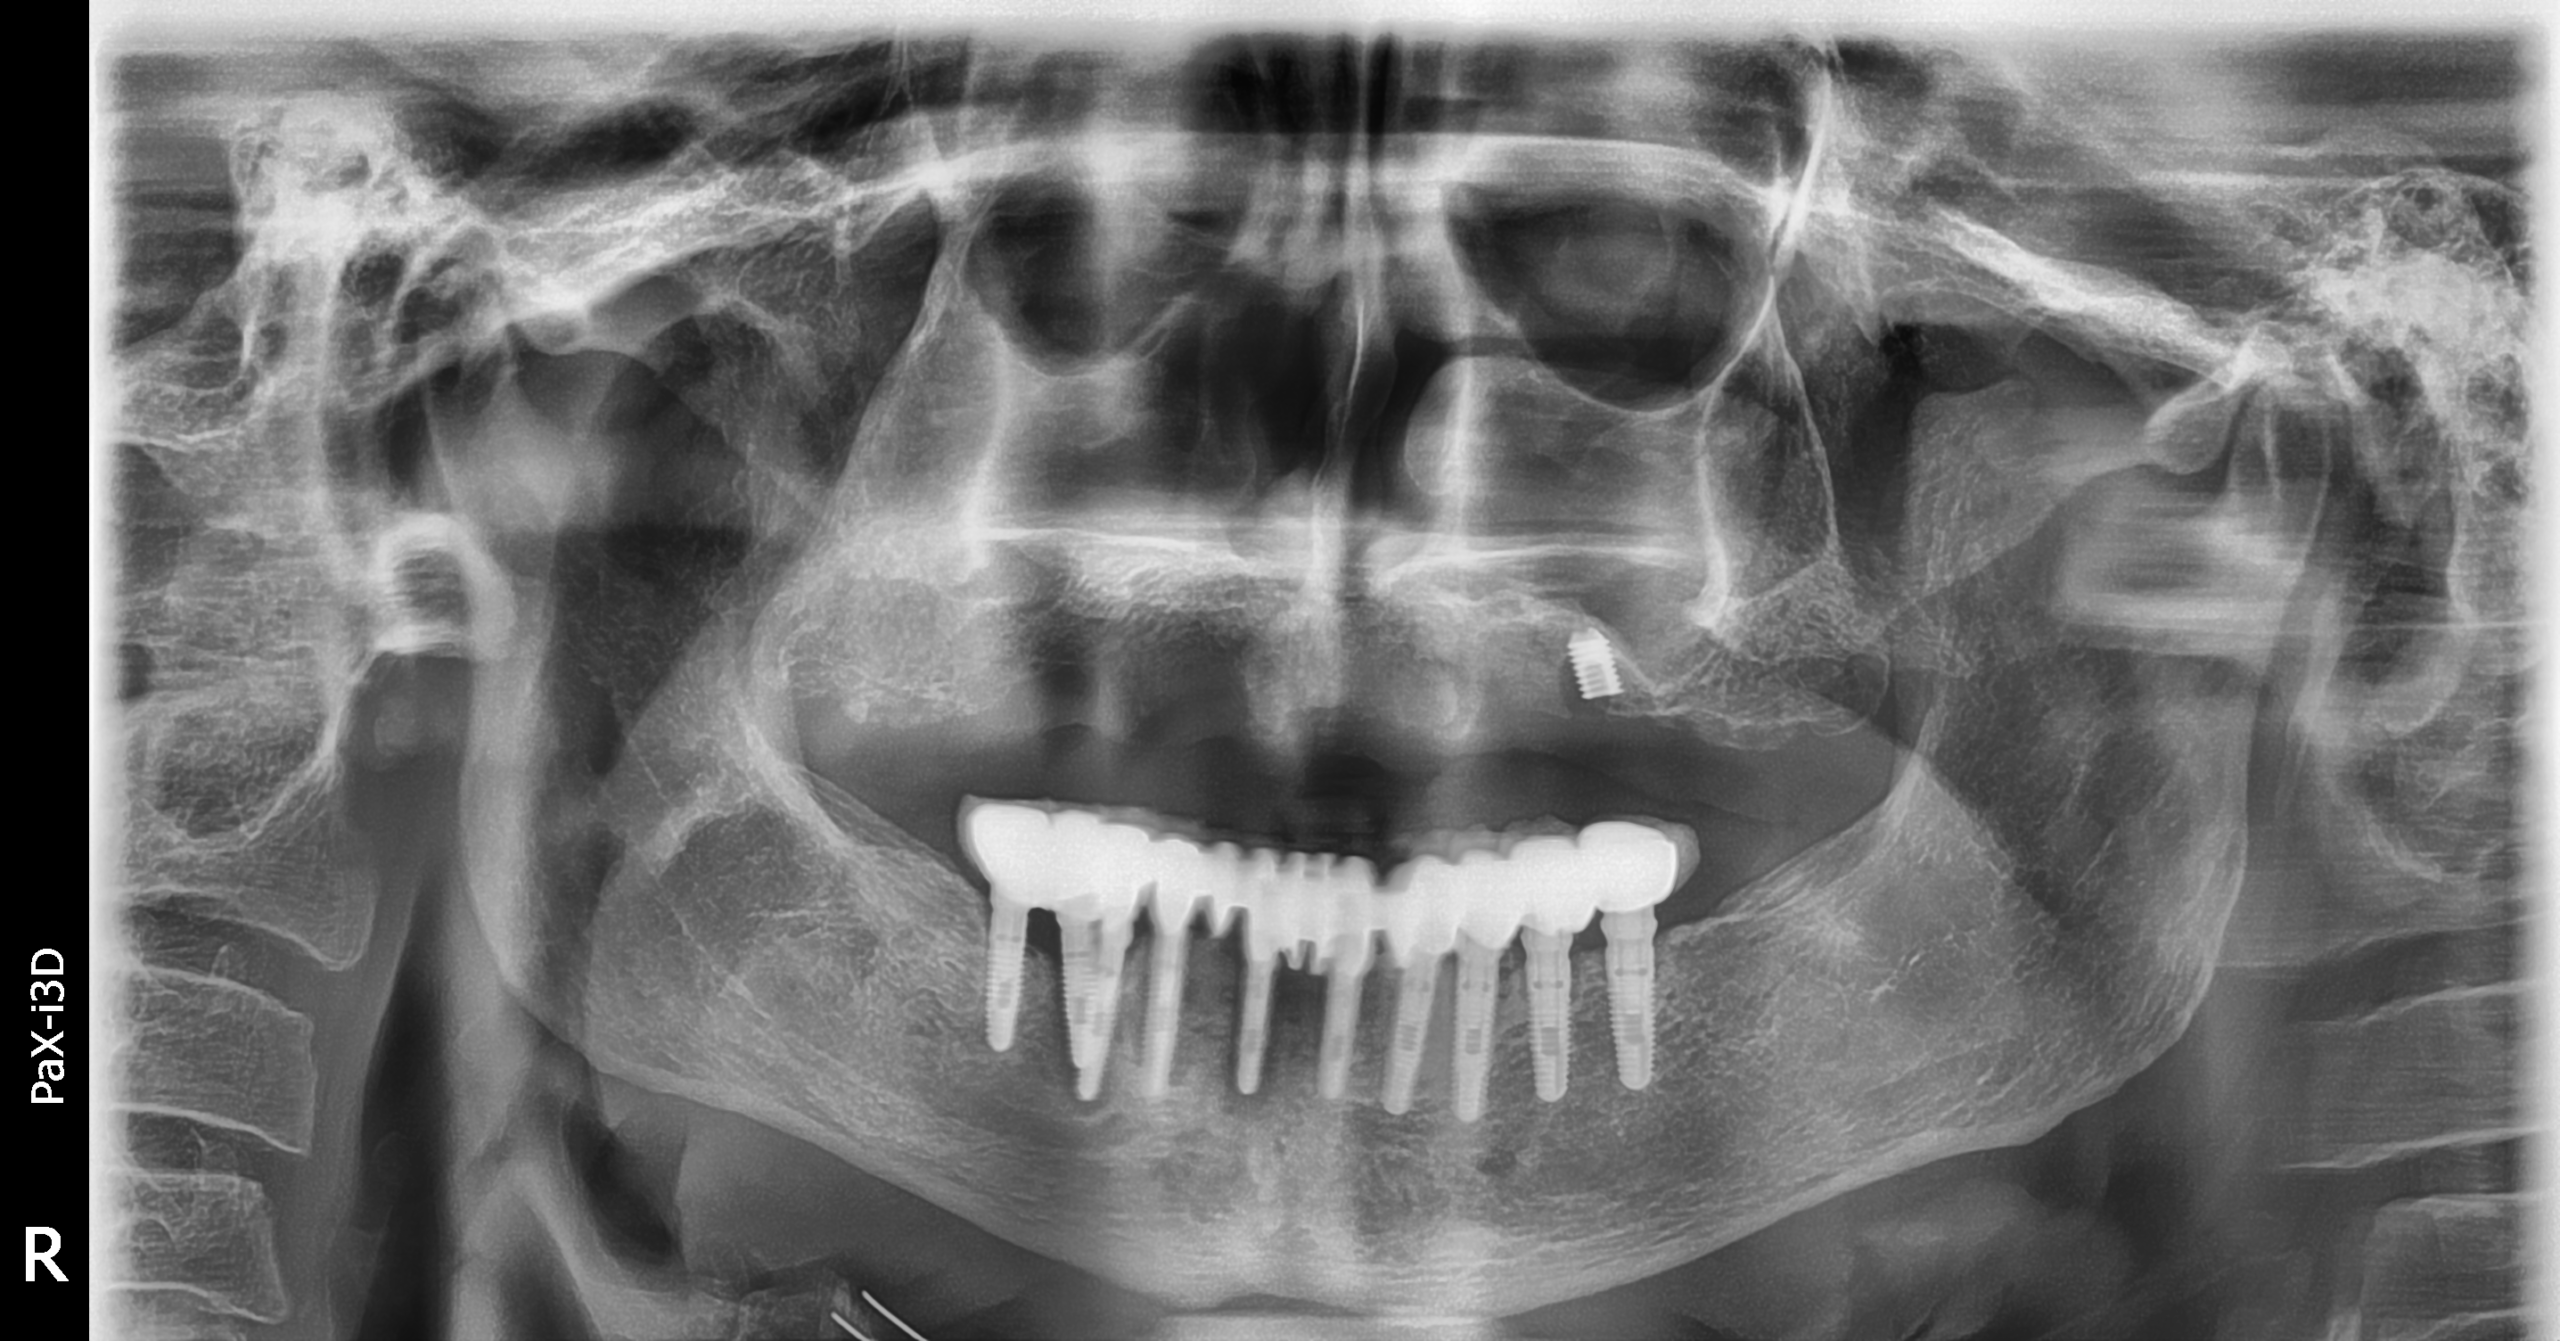

Implantes PCI

Secuencia de imágenes RX, antes y después de la inserción de implantes PCI en la parte superior e inferior de la boca.

Paciente varón de 75 años.

- Radiografía previa a la colocación de implantes Radhex.

- Colocación de implantes Radhex PCI en la parte superior

- Colocación de implantes Radhex PCI en la parte inferior.